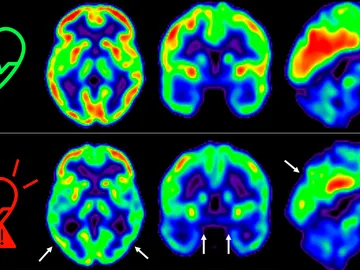

Empezar cuanto antes a cuidar la salud cardiovascular es bueno también para el cerebro